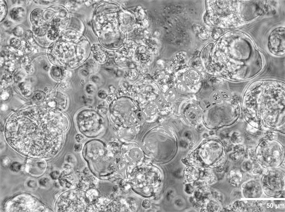

细胞与血液相容性:对 L929 成纤维细胞和 RAW264.7 巨噬细胞无细胞毒性,活 / 死染色显示绿色荧光占比极高。溶血率 < 4%,红细胞形态保持完整,符合生物医用标准。